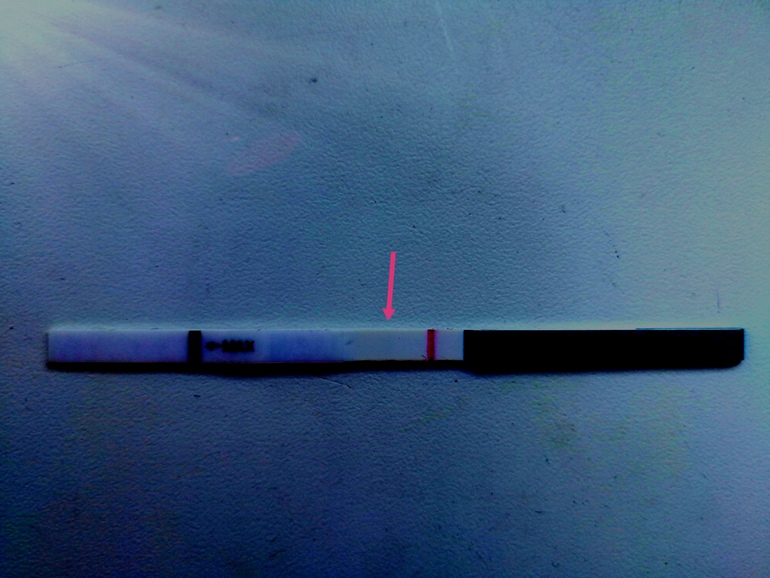

а вот мой

а вот мой